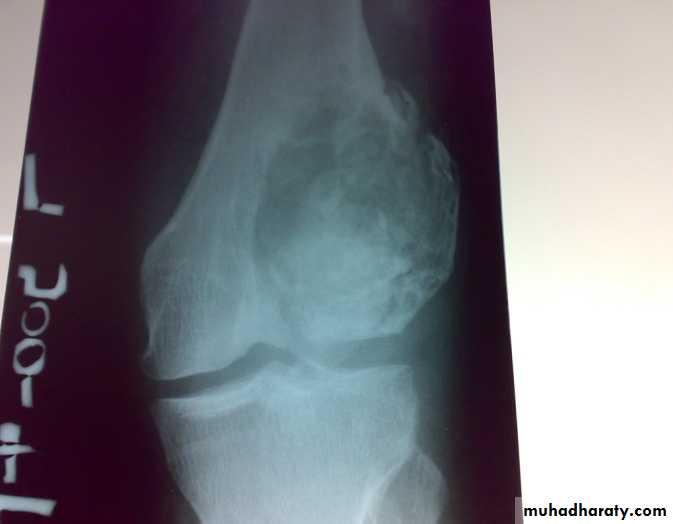

: X-ray are very variable but it show combination of bone destruction and bone formation.

The metaphysis show osteolytic and osteoblastic areas, the cortex is usually perforated and soft tissue shadow may be seen.

There is new bone formation in form of Codman's triangle at periphery of when cortex penetration cause periostium elevation and vertical streaks of calcification in the adjacent soft tissues called sunray appearance.